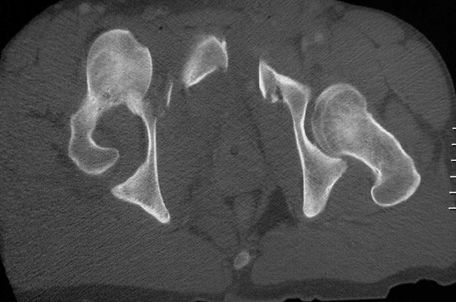

髋关节后脱位

髋关节前脱位

先天性髋脱位